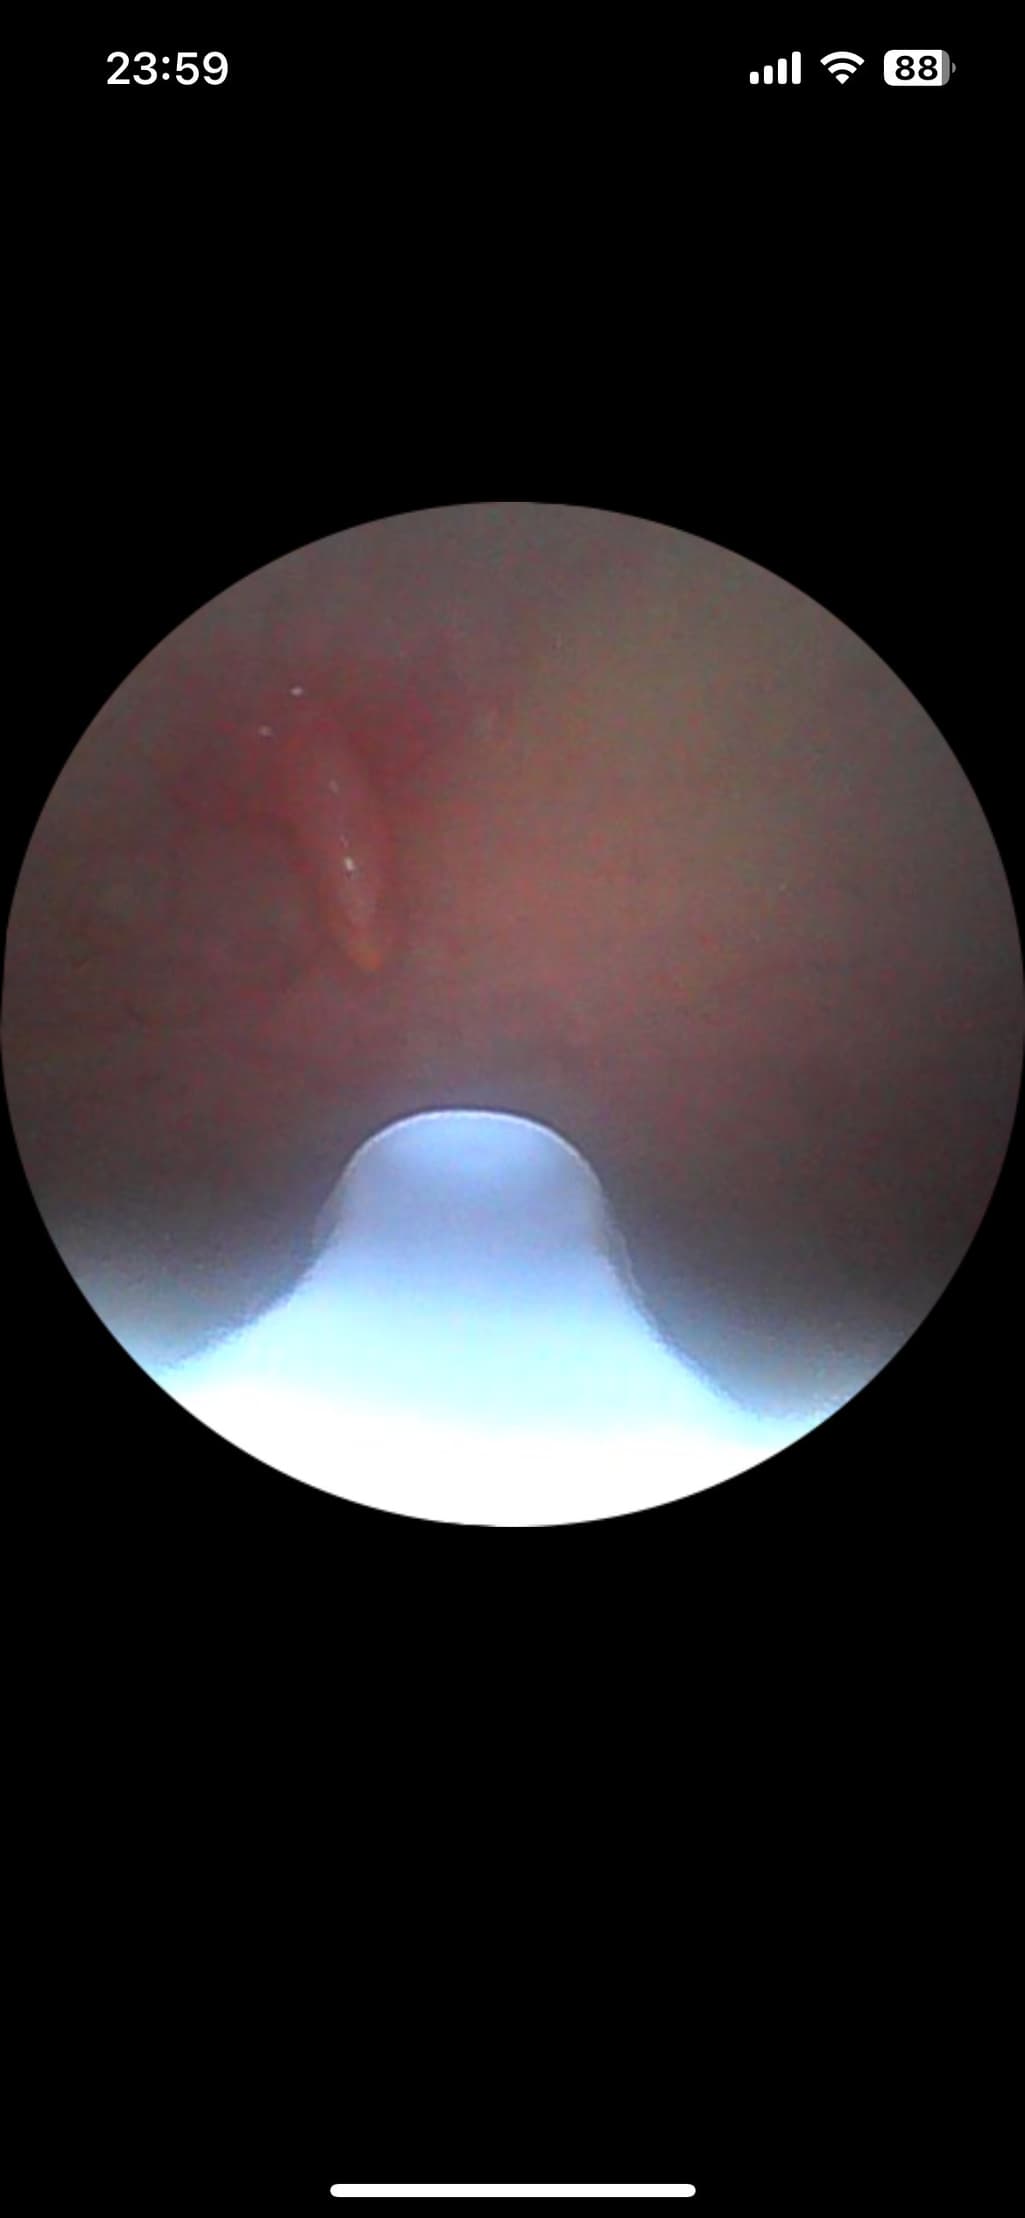

입 안쪽에 연한 천장? 쪽에 뭐가 생겼어요. 혀를 제일 안쪽으로 했을 때 말랑거리는 그쪽이요. 덜렁덜렁거리고 그 부근이 계속 말라서 목이 건조해져요. 건들이면 아프고요. 이게 도대체 뭔가요...? 어제 밤에 갑자기 생겼어요...

사진으로 볼때는 구강 점액낭종의 가능성이 우선 떠오르는데, 해당 질환은 침샘 또는 침샘 관(duct)이 막히거나 손상될 때, 침이 고여 작은 물혹(점액낭종)이 생기는 질환입니다. 보통 말랑하고, 투명하거나 연한 색을 띠며, 덜렁거리거나 움직일 수 있습니다. 대부분 통증은 없지만, 크기가 커지면 불편하거나 건조함, 통증이 동반될 수 있습니다.